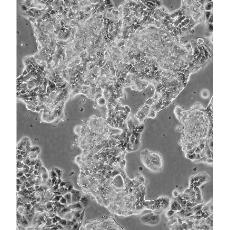

生長(zhǎng)特性 adherent

形態(tài)特征 epithelial

細(xì)胞描述 該細(xì)胞產(chǎn)生高水平的黏液素MUC-1 mRNA,低水平的MUC-2 mRNA,但不表達(dá)MUC-3基因;表達(dá)雌激素受體。